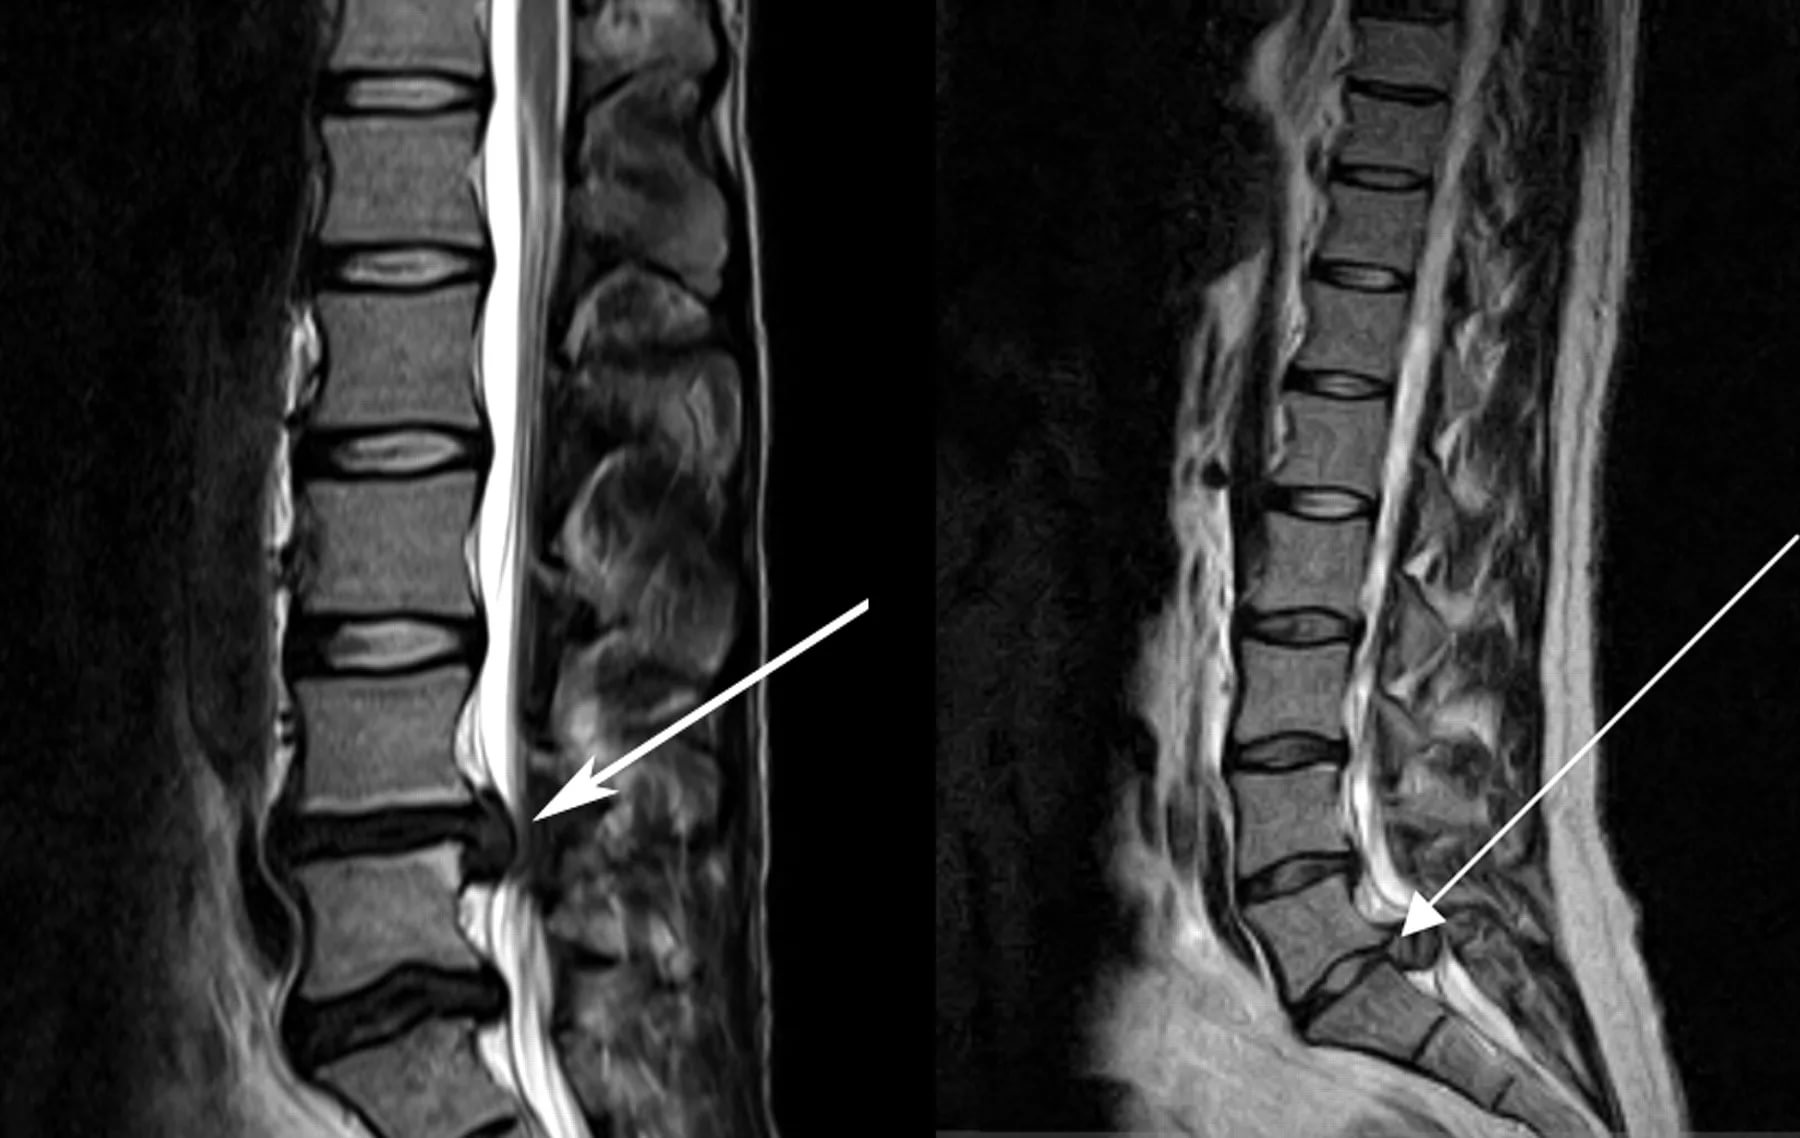

Поясничный стеноз позвоночника

Стеноз позвоночника — это сужение позвоночника, которое может оказать дополнительное давление на спинной мозг и нервы.

Стеноз позвоночника часто возникает в нижней части спины или в поясничном отделе позвоночника, где он может привести к боли в пояснице при ходьбе или стоянии. Пациенты, страдающие этим заболеванием, часто отмечают, что эта боль усиливается, когда садишься или наклоняешься вперед.

Симптомы при нагрузках и особых положениях тела в 90% случаев появляются при поражении нервной системы или дегенеративно-дистрофических процессах в позвоночнике. Диагноз можно подтвердить по результатам магнитно-резонансной томографии поясничного отдала позвоночника, реже используется КТ или рентген (малоинформативные). Болевой синдром в области поясницы может свидетельствовать о следующих заболеваниях: